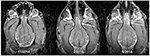

In the second case, a 12-year old Golden Retriever was experiencing seizure activity. Awake MRI detected a frontal lobe mass that was the likely cause of the epileptic events. The observation of Berns/Spivak was corroborated by one of the paper’s co-authors, Sarah Nemanic, a veterinary radiologist at the Carlson College of Veterinary Medicine, Oregon State University.

In the fourth case, a 3-year old Boxer/Hound was experiencing experiencing epileptic seizures of increasing frequency and severity. Awake MRI detected ventriculomegaly that was a potential cause of the seizure activity. The Berns/Spivak observation was confirmed by Dr. Nemanic. The owner then took the MRI film to her dog’s veterinary neurologist to discuss whether such knowledge should prompt an adjustment in the treatment regimen.